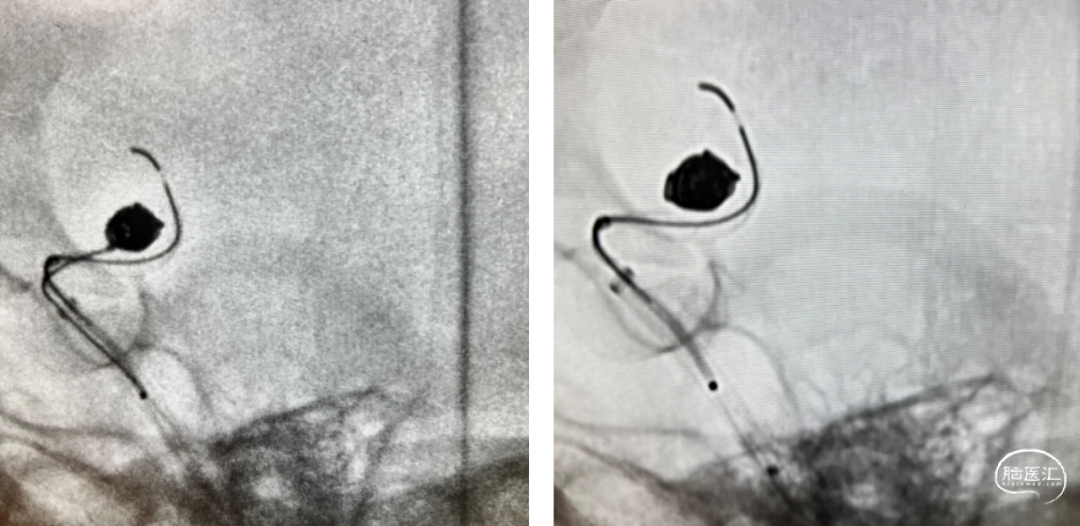

【XT-17超选入动脉瘤腔内】

【Perfiller®4mm*8cm-3D半推入】

利用微导丝引导XT-27支架微导管置于大脑中动脉远端,然后将泰杰伟业TJED-D-5.0-14 Nuva®血流导向密网支架(预期血管直径和长度4.5mm*19mm)沿着支架微导管顺利输送到位。

缓慢回撤微导管,在颈内动脉末端处,影像下观察支架头端轻松打开,确认支架远端锚定区域,完成远端定位后,采用推拉结合方式缓慢稳定释放Nuva®支架至完全覆盖动脉瘤瘤颈口,并确保支架贴合打开情况良好。